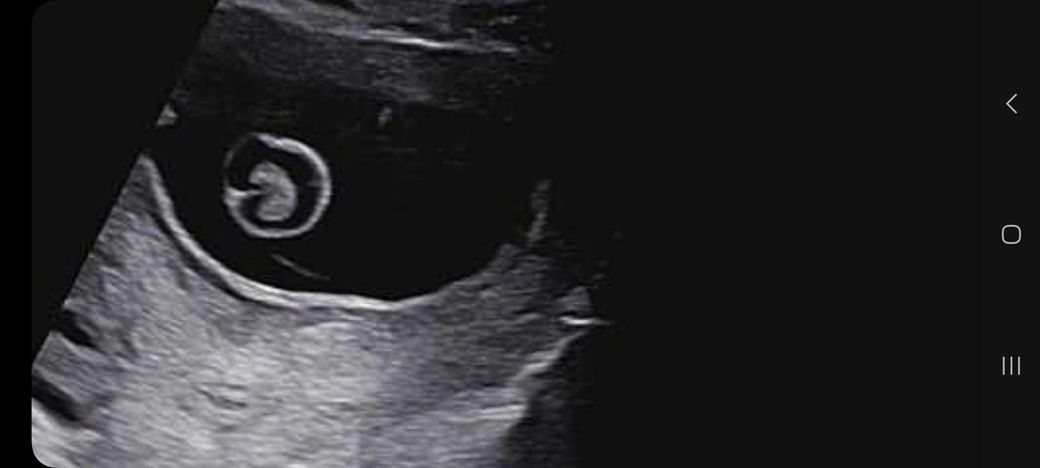

임신 10주차가 되었고 오늘 초음파 사진을 찍고왔어요

다 잘 크고있는데

머리 뇌 모양이 나비 모양이 아니라

2주뒤에 초음파 사진 볼 때 한번 더 보자 하더라구요

나비 모양이 되야 정상? 인데 아니라 신경이 쓰이네요

어떻게 보시는지 의견을 들려주심 감사합니다.

• 3번 째 사진